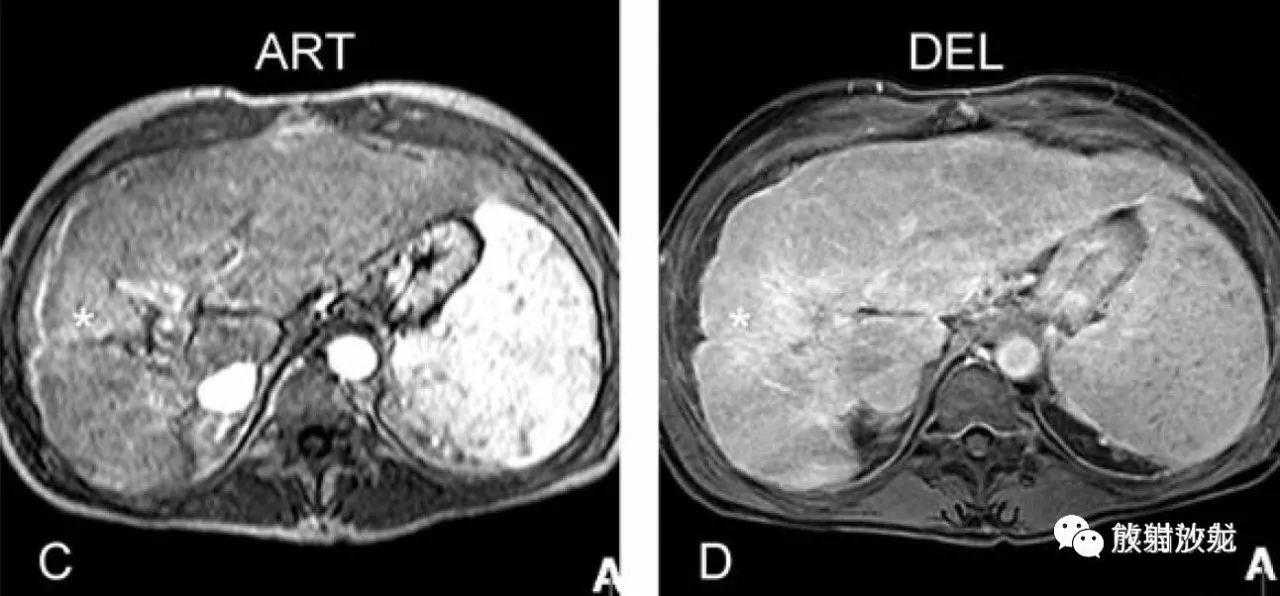

T2fatsat:T2压脂,肝右叶局部萎缩并信号增高;

T1反相位:相应部位呈较低信号;脾大,脾实质内可见GamnaGandy小体,提示门脉高压;

ART:动脉期有强化,可能提示HCC;

DEL:延迟期右叶病灶持续强化呈等信号,提示融合性纤维化。

肝硬化,融合性肝硬化,MRI表现:

A~D:影像表现同上方所述。